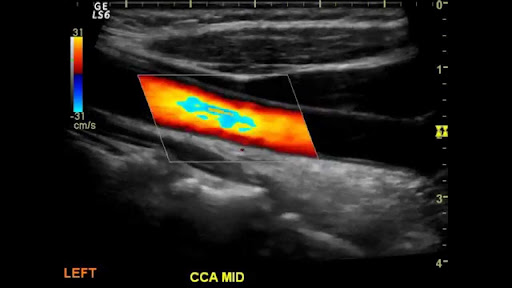

Nov 03, 2021 · revascularization of carotid arteries involves the removal of blockages in the carotid arteries, which improves the circulation in the carotid arteries. Normal Carotid Duplex - YouTube

Normal Carotid Duplex - YouTube from i.ytimg.com